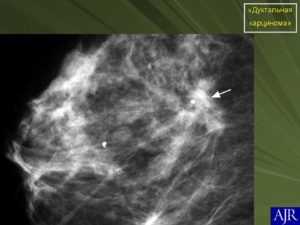

Внутрипротоковая карцинома in situ

Внутрипротоковый или дуктальный рак in situ в специальной литературе обозначается аббревиатурой DCIS. В каждом третьем случае он развивается сразу в нескольких очагах — мультицентрично.

Как правило, DCIS проявляется симптомами — кровянистыми выделениями из соска, есть специальный термин — «кровоточащая молочная железа», отражающий её основной, но не обязательный клинический признак. Могут беспокоить боли и припухлость. При размере больше сантиметра DCIS можно прощупать. При маммографии патологию визуализируют по глыбкам кальция и уплотнению тканей.